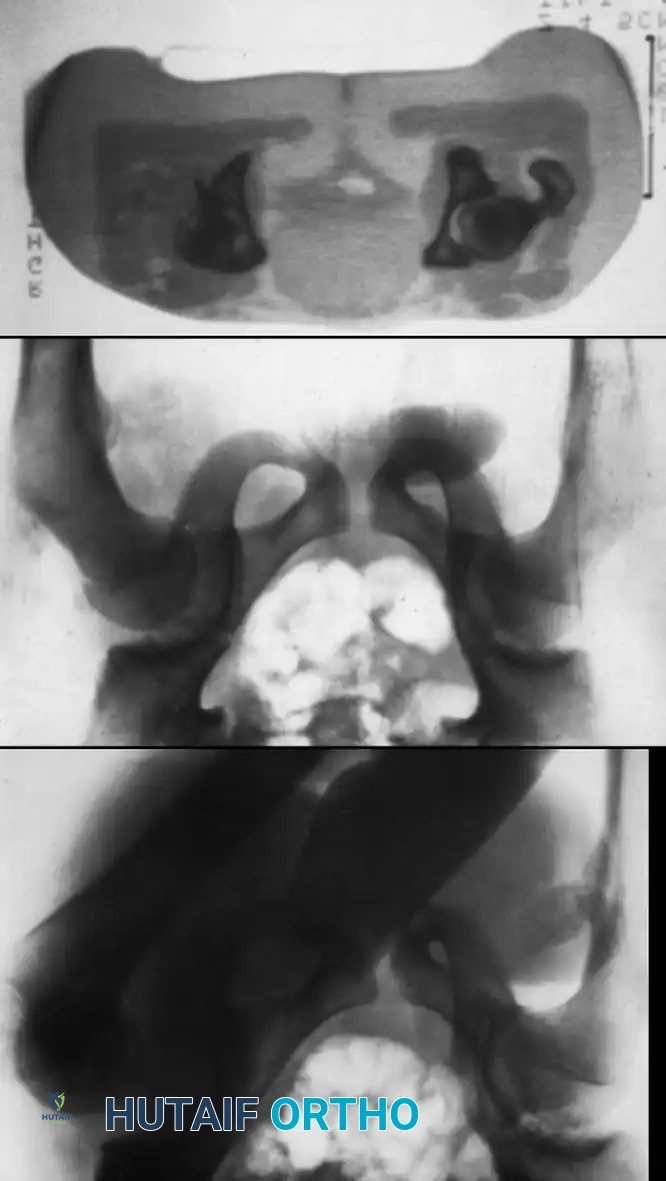

Fig. 33-126 Incongruous reduction of hip. Radiograph of both hips after what was thought to be successful closed reduction of traumatic dislocation of the right hip in adolescent. Reduction is incongruous, however, as shown by break in Shenton line and increase in width of joint space.

Fig. 33-127 Incongruous reduction of hip. A, Traumatic hip dislocation in adolescent. B, After two attempts at closed reduction, joint space is still too wide and Shenton line is broken. C, CT scan shows osteocartilaginous fragment in acetabulum impeding reduction; open reduction was necessary.